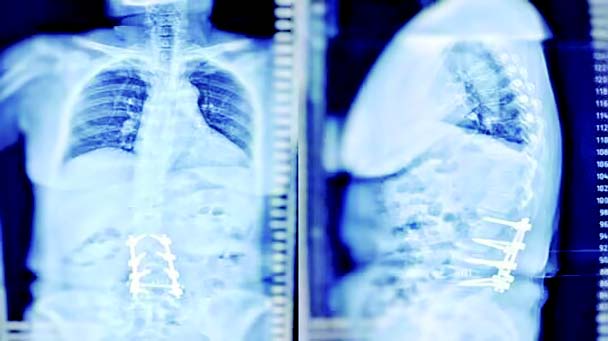

患者术后脊柱全长位片

经过多方会诊,最终陈成团队确定了患者的手术方案,即在不影响手术效果的情况下,进行腰2至腰5的椎弓根钉固定;腰4、5椎管减压、椎间融合;腰5骶1椎间盘突出仅仅行左侧椎板开窗髓核摘除,避免术中多节段融合的出现。手术中,陈成团队有条不紊,合作无间。术后,患者的下肢疼痛麻木症状明显缓解,复查脊柱全长位片,显示腰椎侧弯基本矫正。